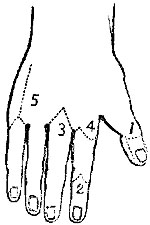

The four plates which precede the letterpress were drawn on wood (from original photographs) by Mr. D.W. Williamson, Melbourne Place, and the lines of incision for the various operations were added by the author.

The rough woodcuts scattered through the work were drawn on wood by the author, and for their roughness he, not his engraver, is responsible. He also hopes that the references in the letterpress will be accepted as sufficient acknowledgment of the true ownership, in those few instances in which the idea of the diagram has been borrowed.